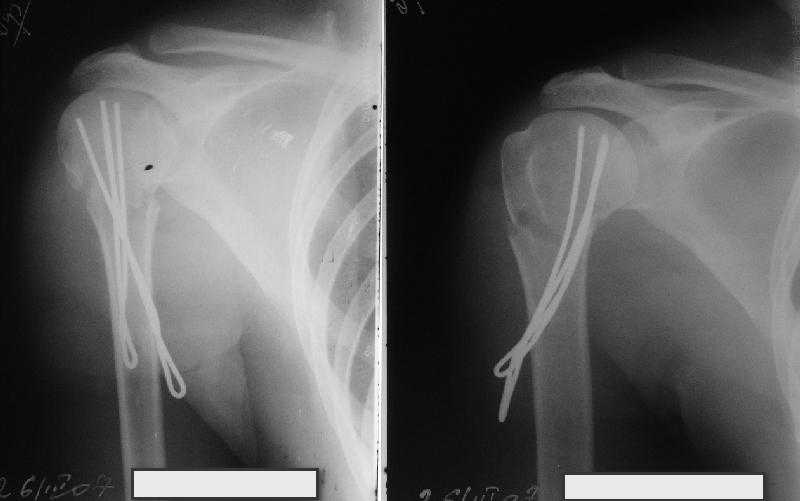

Re: Перелом шейки плеча - тактика?

Сделали напряженными спицами по методике А.Ф.Лазарева со товарищи Репозиция сделана спицевым дистрактором, проксимальная спица была проведена в полскости деформации перпендикулярно оси наклонившейся головки. Получилось все довольно легко. Спицы малость покороче можно было сделать, ну да удалять потом легче будет.

Картинка в приложении.